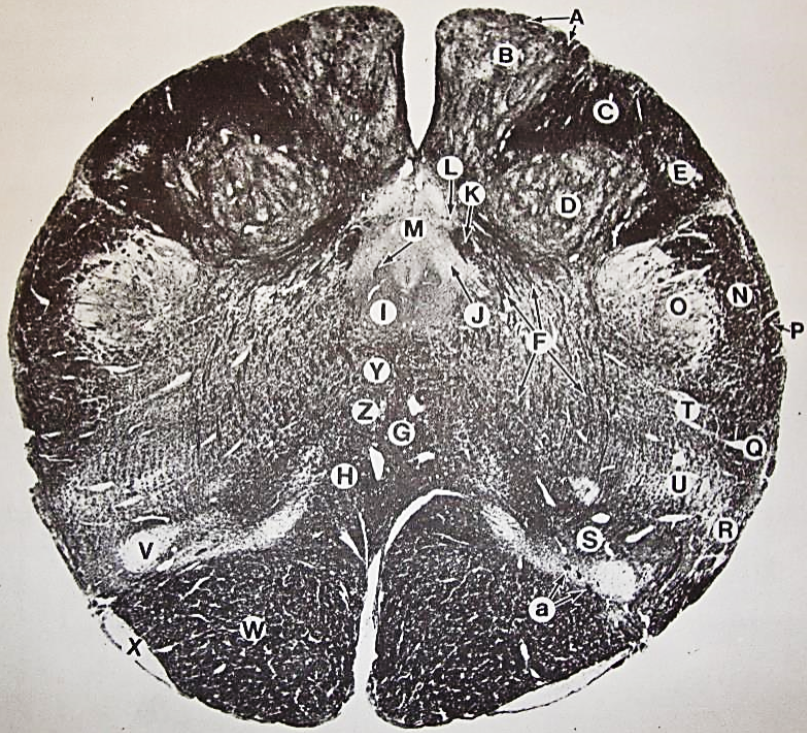

A

fasciculus gracilis

B

gracile nucleus

C

fasciculus cuneatus

D

cuneate nucleus

F

internal arcuate fibers

G

decussation of internal arcuate fibers

H

medial lemniscus

I

hypoglossal nucleus

J

dorsal motor nucleus vagus

K

solitary fasciculus

L

solitary nucleus

M

dorsal longitudinal fasciculus

N

spinal trigeminal tract

O

spinal trigeminal nucleus

P

posterior spinocerebellar tract

Q

anterior spinocerebellar tract

R

spinal lemniscus

S

lateral vestibulospinal tract

T

rubrospinal tract

U

lateral reticular nucleus

V

medial accessary olivary nucleus

W

pyramidal (corticospinal) tract

X

arcuate nucelus

Y

medial longitudinal fasciculus

Z

tectospinal tract

a

fascicles of hypoglossal nerve